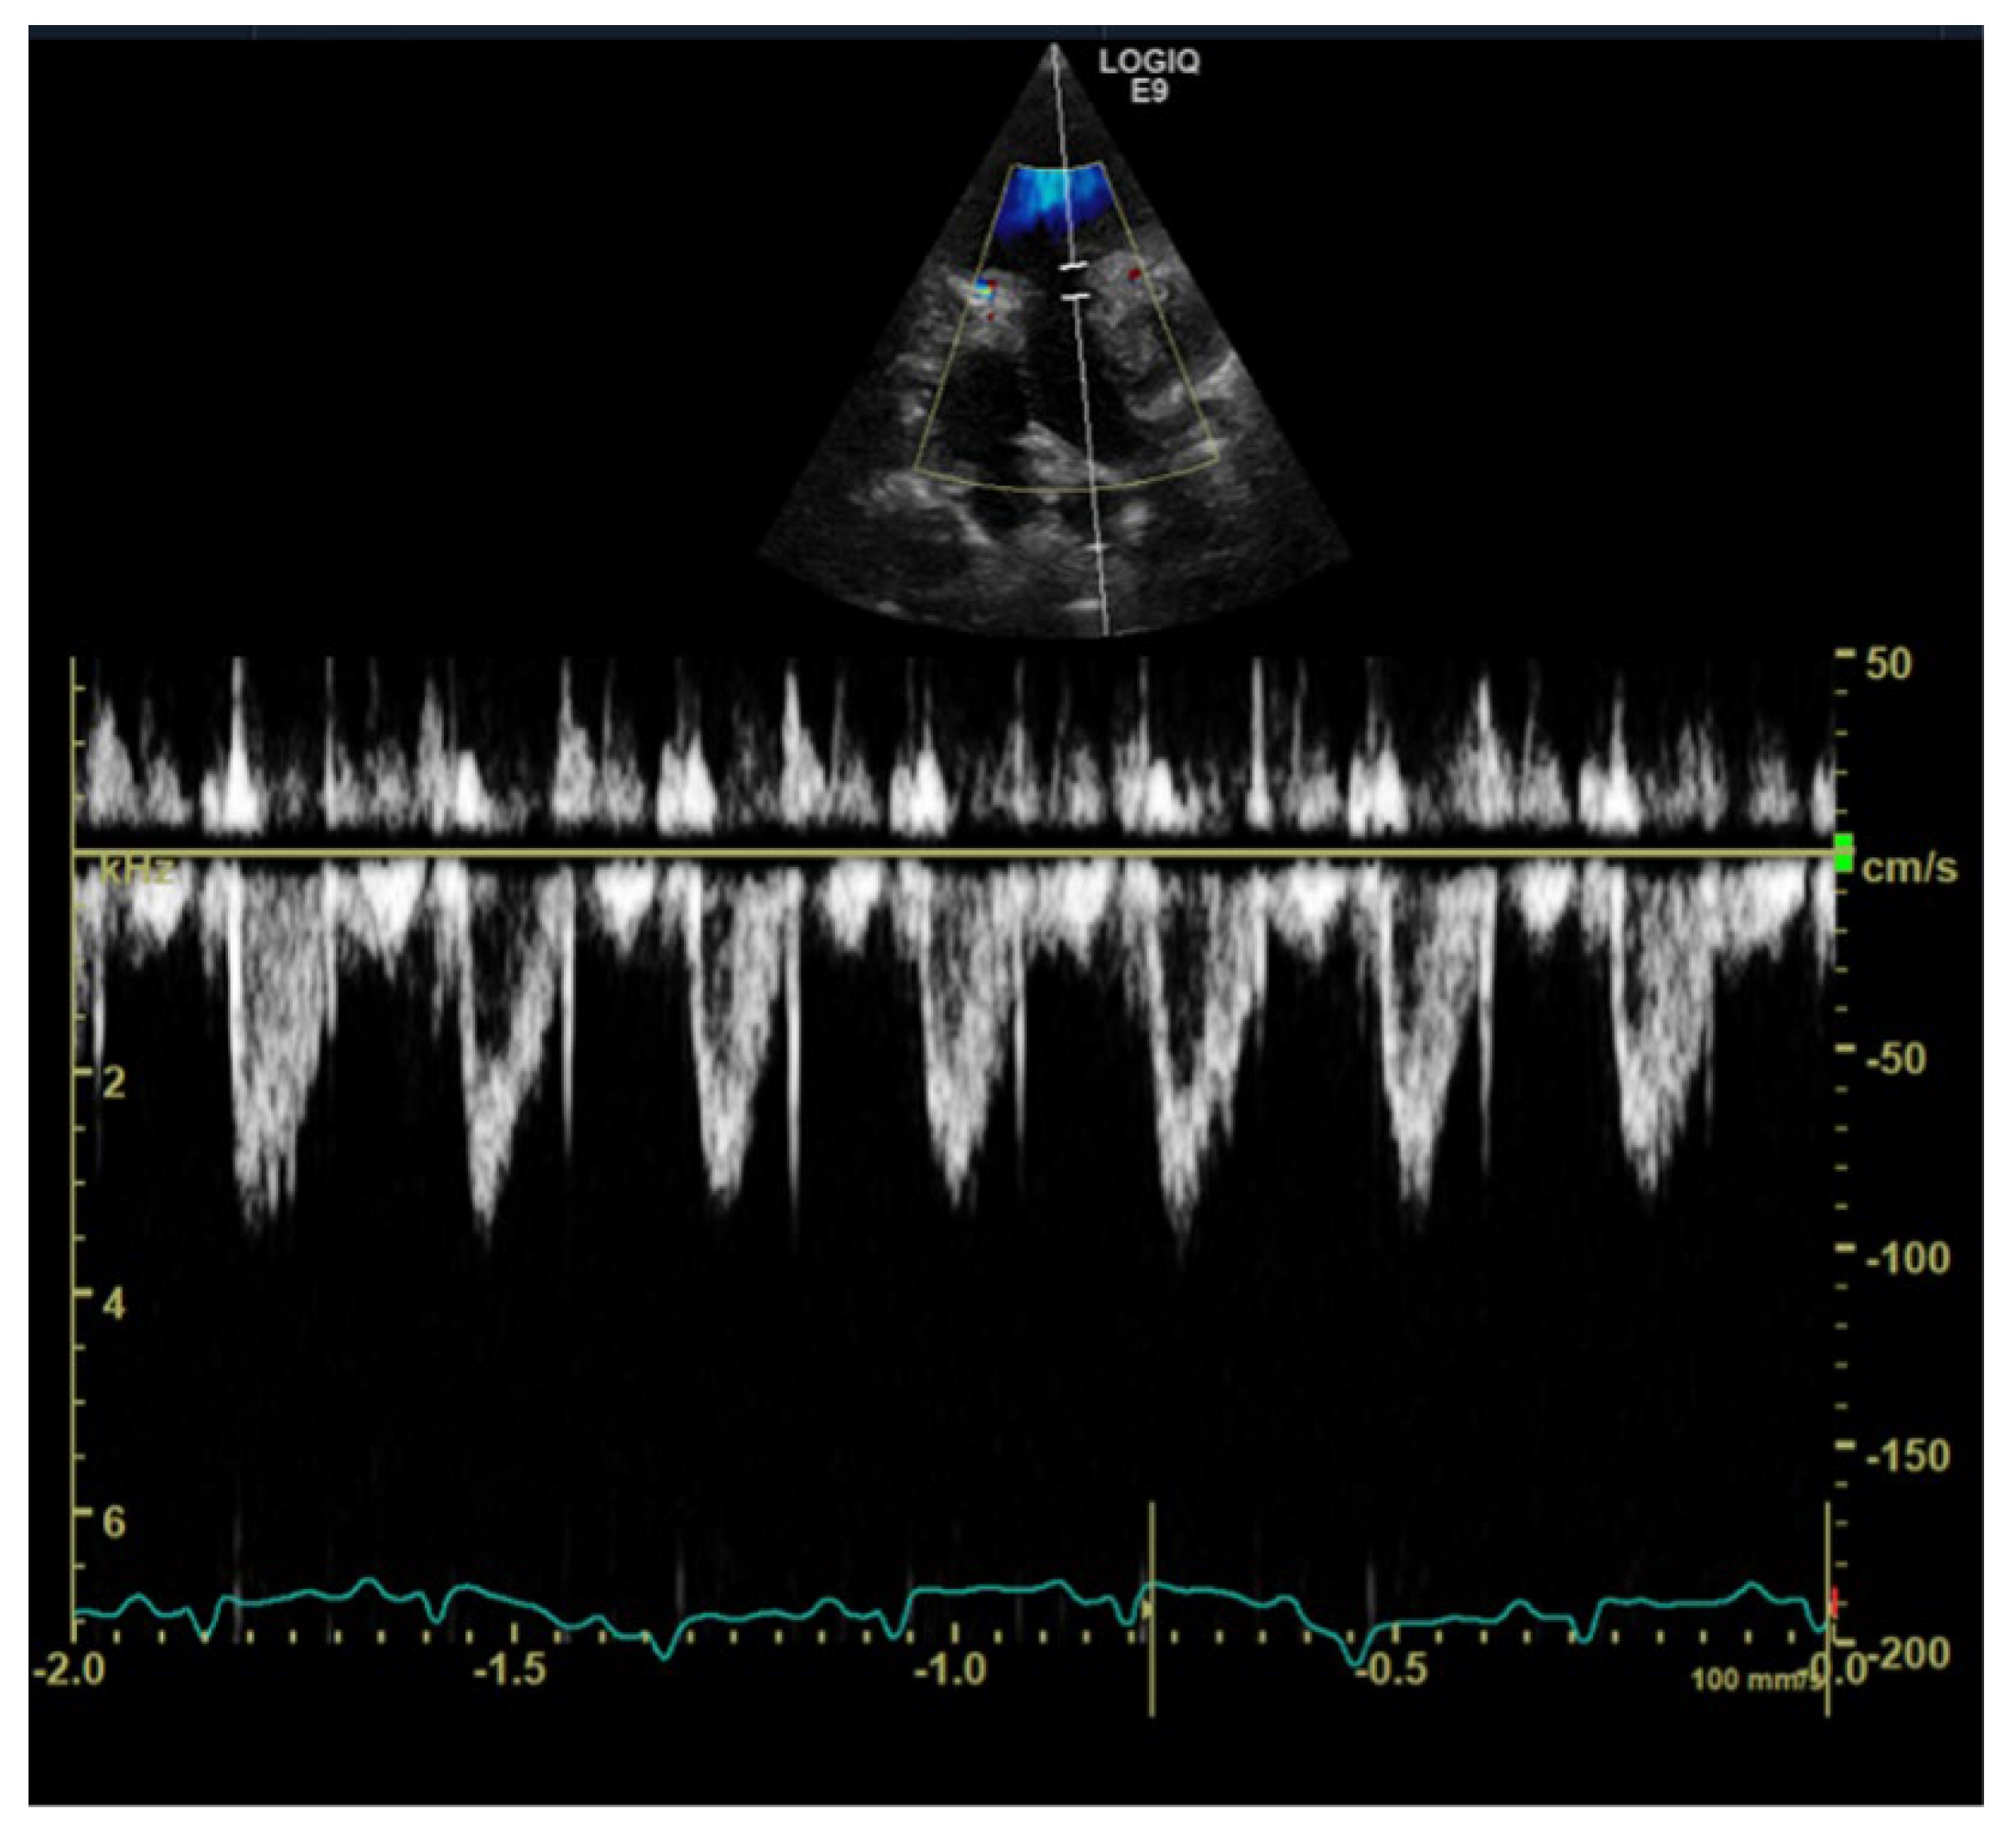

1. Case Description